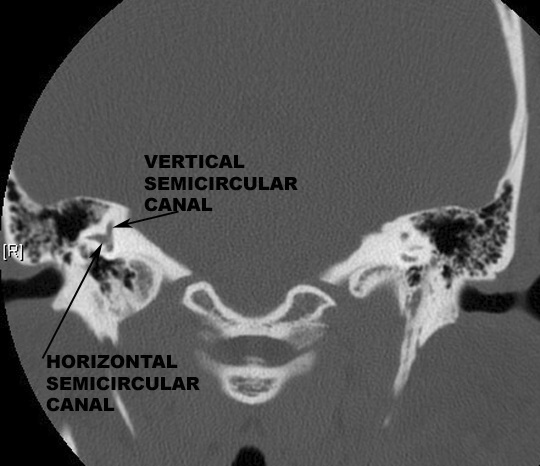

Identify the semicircular canals. Click the image for labeling.